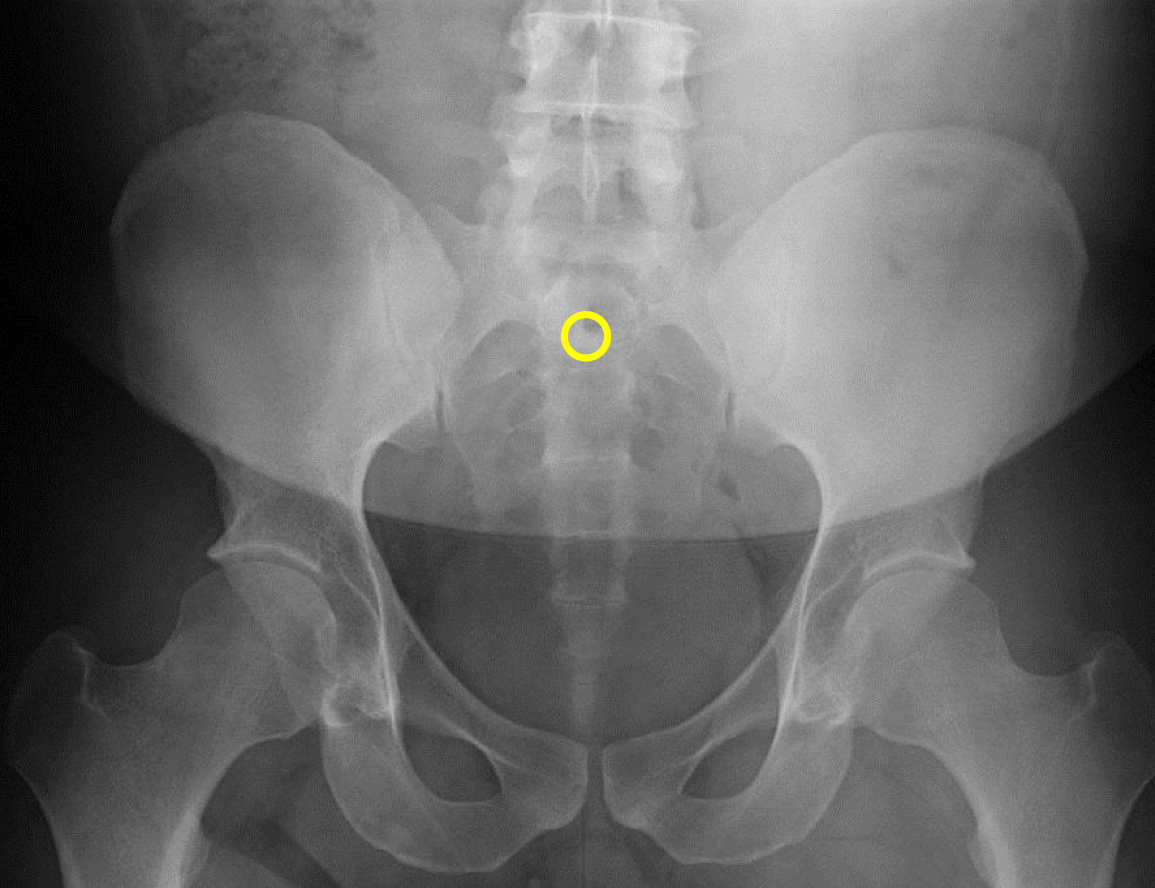

What view is this?

AP (Anterior to Posterior) LumboPelvic

What is this?

Femur Heads

What is this?

Superior Iliac Crests

What is this?

Lateral Iliac Crests

What is this?

Ischial Tuberosites

What is this?

Obturator Foramen

What is this?

S2 Tubercle

What is this?

Pubic Symphysis

What is this?

Sacral Groove

What is this?

Lateral aspect of sacrum

What is this?

Medial Aspect of Ilium